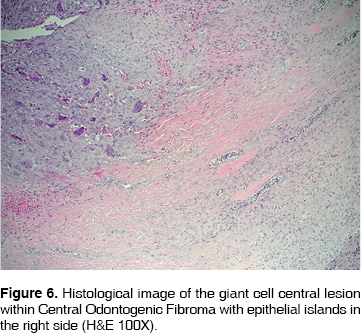

Histological features: the tumor was conformed by fibro-cellular tissue vascularized forming cross linked bundles of fusiform cells with scarce production of collagen, between them islands and strands of non active odontogenic epithelium were found. In some zones specially in the outer area, there was a highly vascularized fibro-cellular tissue where could be found many osteoclastic giant multinucleated cells type, distributed around vessels and some intralesional hemorrhages (Figures 6 and 7).

The case here reported histologically is formed by fibro-cellular tissue well vascularized forming cross linked bundles of fusiform cells and scarce production of collagen fibers, abundant strings and islands of inactive odontogenic epithelium. In some areas of the fibro-cellular tissue many giant multinucleated osteoclast type cells may be identified specially around the blood vessels and intralesional hemorrhage zones. These findings are similar to those described in the previously reported cases.